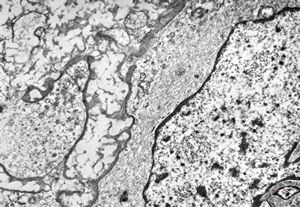

oral saprophytic bacterium